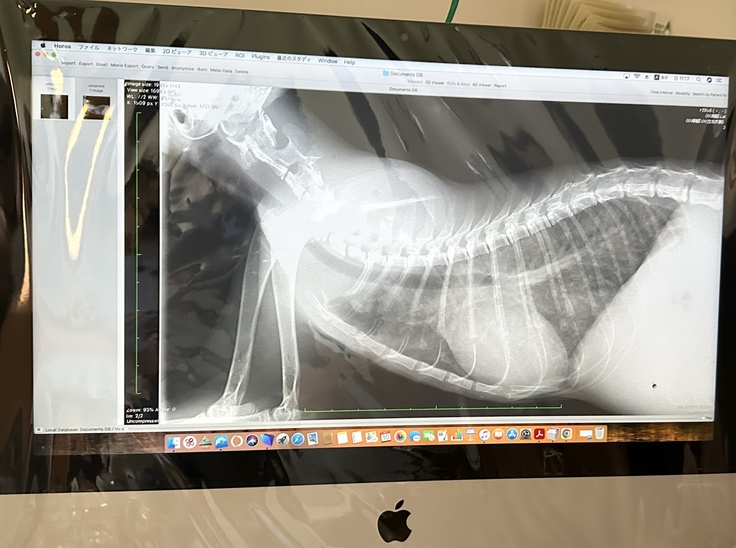

病状説明では...

①両肺にびまん性の陰影多数あり

•FIPでこの症状が出るとは考えにくい

•舞い上がる猫砂を吸い込んだ可能性あり

•何らかのウイルス感染によるもの

②右心房肥大

•肺が機能しておらず、充分な血流を心臓に送ることができなかったことで心臓に負担がかかってしまった

FIPに関しては良くもなっていないが、さほど悪くもない。少しずつではあるが改善に向かっていると考えていいのではないか。

1度肥大した心臓は元には戻らない。肺が良くなっても2〜3年の寿命である。

入院時と本日のレントゲンを見ても、あまり改善は見られませんでしたが、今やれることはこれぐらいしかないということでした。

FIP治療薬.抗生剤.ステロイドを併用して経過観察となりました。